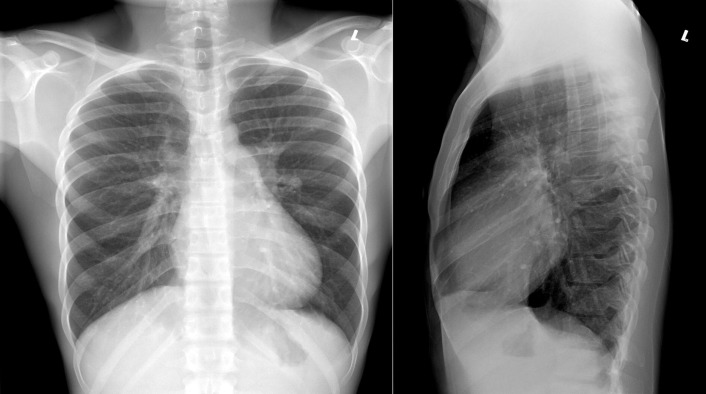

A patent foramen ovale is present in 25% to 30% of the adult population ( Figs. 18-1 to 18-4 ). Any magnitude of shunting across it in normal circumstances is undetectable radiographically. Percutaneous patent foramen ovale closure devices are fairly commonly inserted and are radiographically evident.